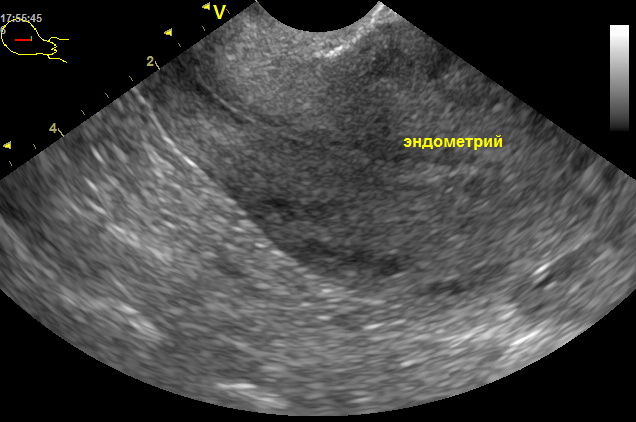

Медицинская диагностика: Гиперплазия эндометрия на УЗИ